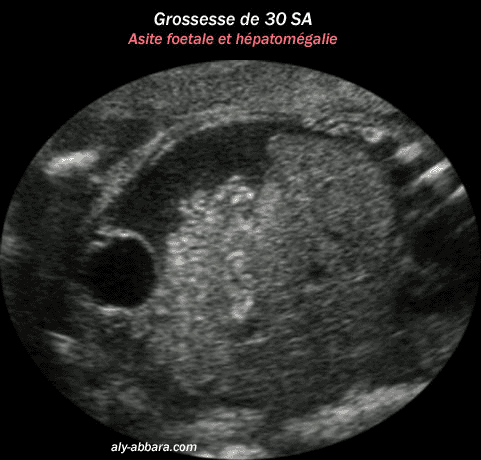

Grossesse de 30 semaines d'aménorrhée avec la mise en évidence d'une ascite fœtale

avec une hépatomégalie et une hyperdensité digestive modérée

Il s'agit d'une infection fœtale multiviscérale à Parvovirus B19.